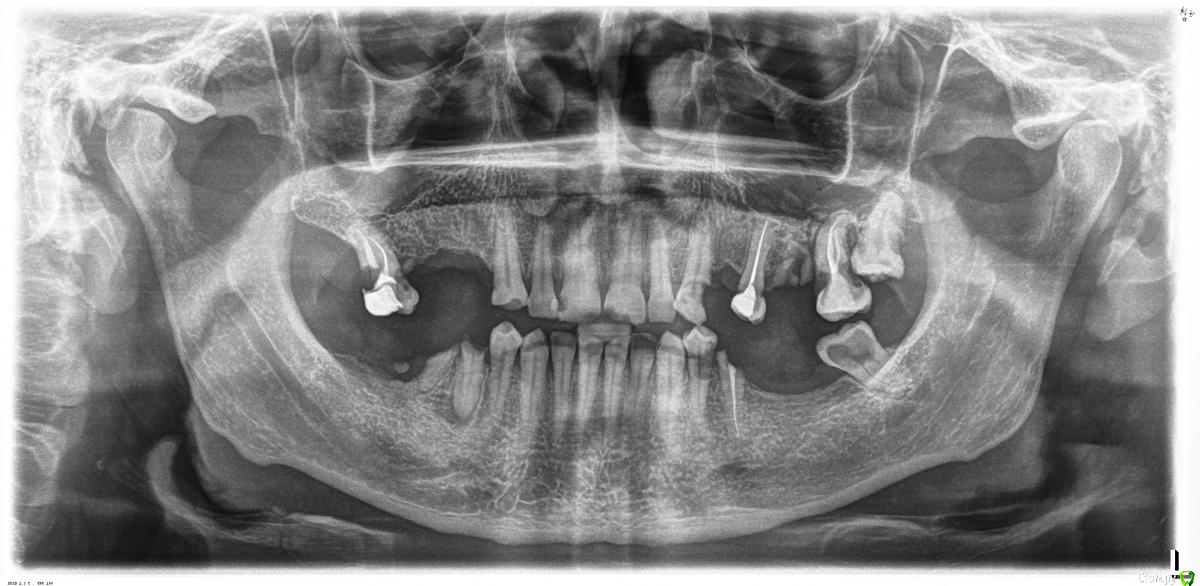

chucha Опубликовано 19 января, 2016 Поделиться Опубликовано 19 января, 2016 Доброго всем времени суток. Как и у многих боязнь всего, что связано с зубами сделала свое дело.Посоветуйте с чего начать, от чего точно избавиться, за что еще побороться. Заранее спасибо. Ссылка на комментарий

IvanK Опубликовано 20 января, 2016 Поделиться Опубликовано 20 января, 2016 Удалять 17, 25?, 26, 27,28, 38, 35?, 45, 46Лечить: ... почти всеСоветую начать с консультации ортопеда Ссылка на комментарий